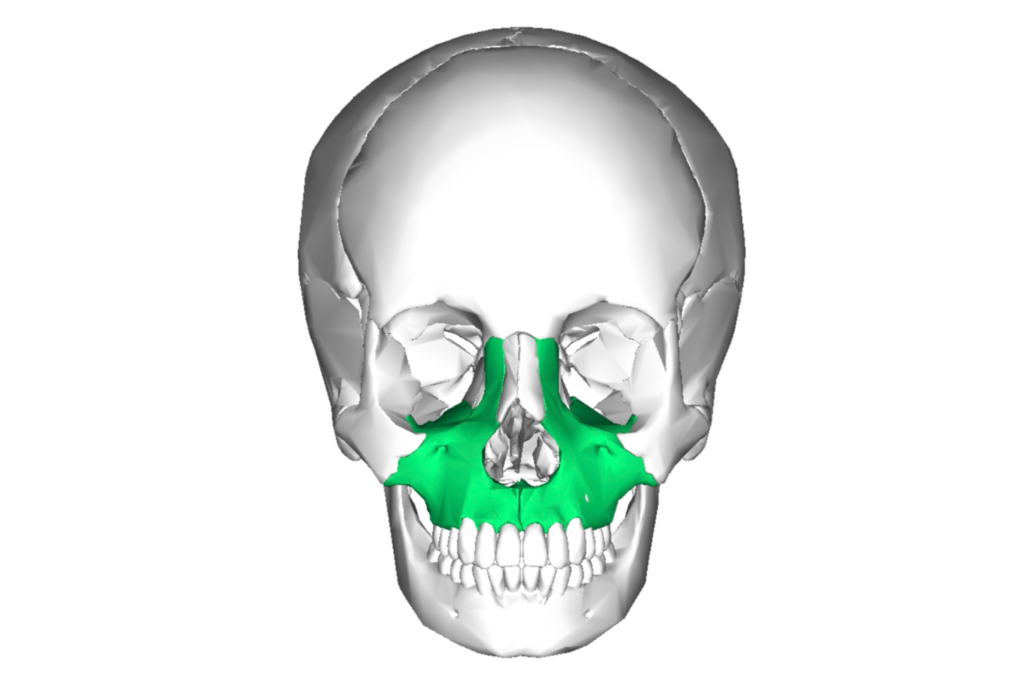

Craniofacial Growth Guidance is proactive and therapeutic approach in dentistry and orthodontics which monitors and steers the development of a child’s jaw, face and airway into proper alignment during the peak growth years. The treatment intervenes early to address narrow palates, primary crowding, crossbites, receding jaws, breathing issues and signs and symptoms of sleep disordered…